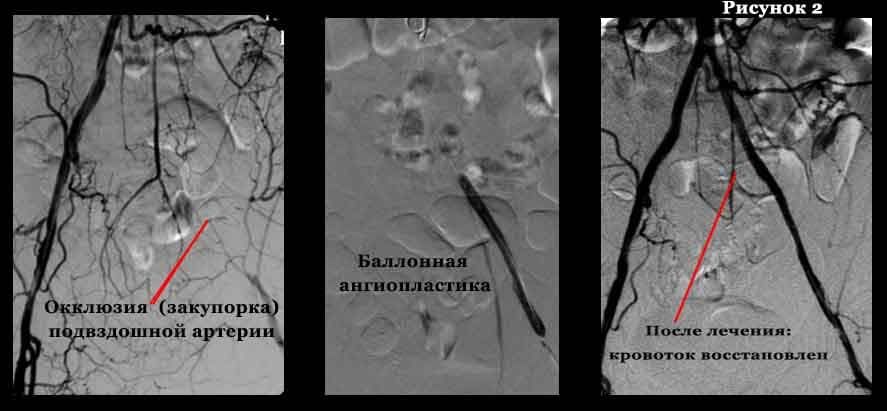

Атеросклеротические изменения артерий нижних

Атеросклеротические изменения артерий нижних 109 фото